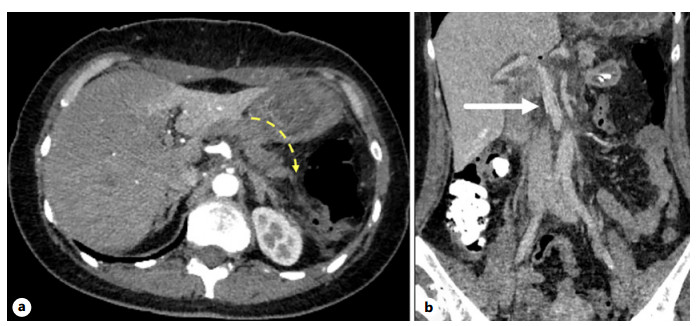

Abstract: Intraductal papillary mucinous neoplasm (IPMN) and solid pseudopapillary neoplasm (SPN) are uncommon cystic tumors of the pancreas. The simultaneous occurrence of these 2 pancreatic neoplasms is extremely rare. We present a case of synchronous solid SPN and IPMN – carcinoma in a 44-year-old female patient. An uncommon surgical treatment was performed – pancreatoduodenectomy with the resection of the pancreas body, resection of the mesentericoportal trunk + distal pancreatectomy, and splenectomy. Part of the pancreatic tissue was preserved.